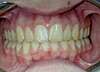

Cas n°2

Malpositions incisives et canines chez une jeune fille de 13 ans.

Durée du traitement: 2 ans.